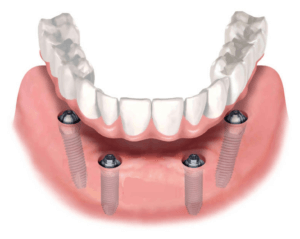

Зубной мост может крепиться к имплантатам. Они заменяют классические мостовидные и съемные конструкции.

Например, несъемный покрывной протез для имплантации по технологии All-on-4, заменяет полную съемную конструкцию. Главное преимущество — надежное прикрепление к челюсти. Человек может полноценно жевать и разговаривать без стеснения.